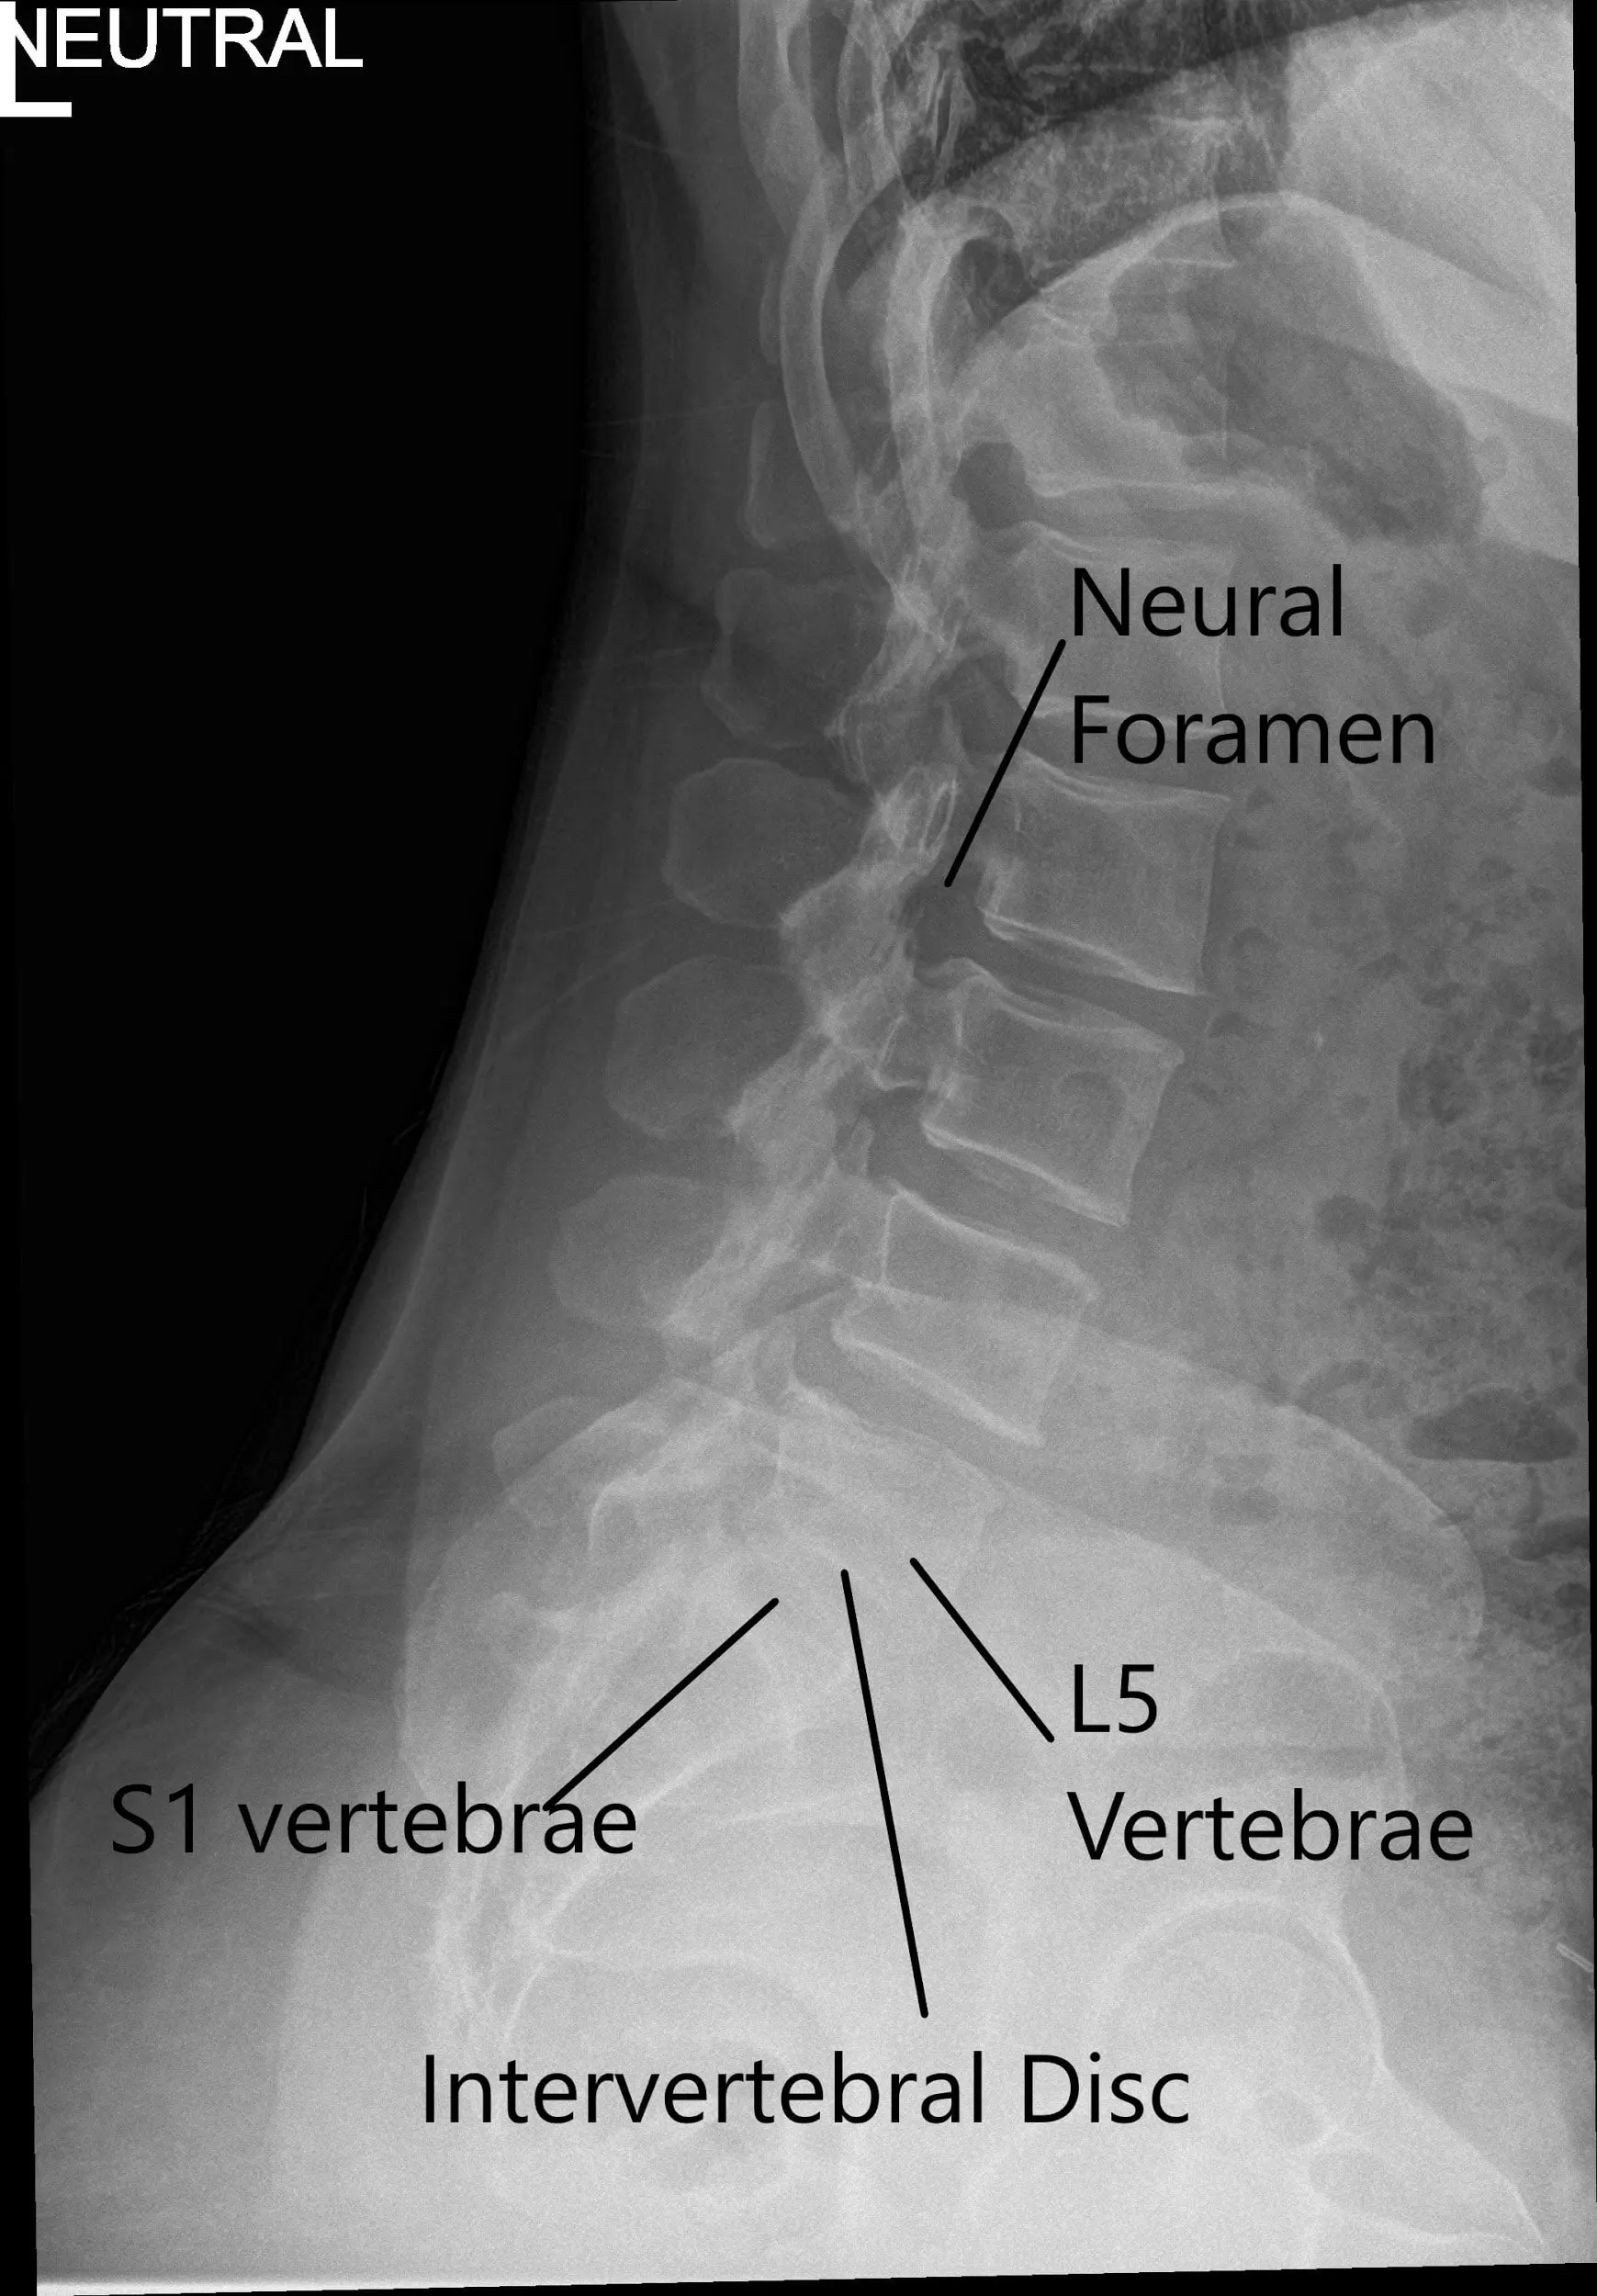

X-ray of the LS spine in AP and Lateral views showing degenerative changes.